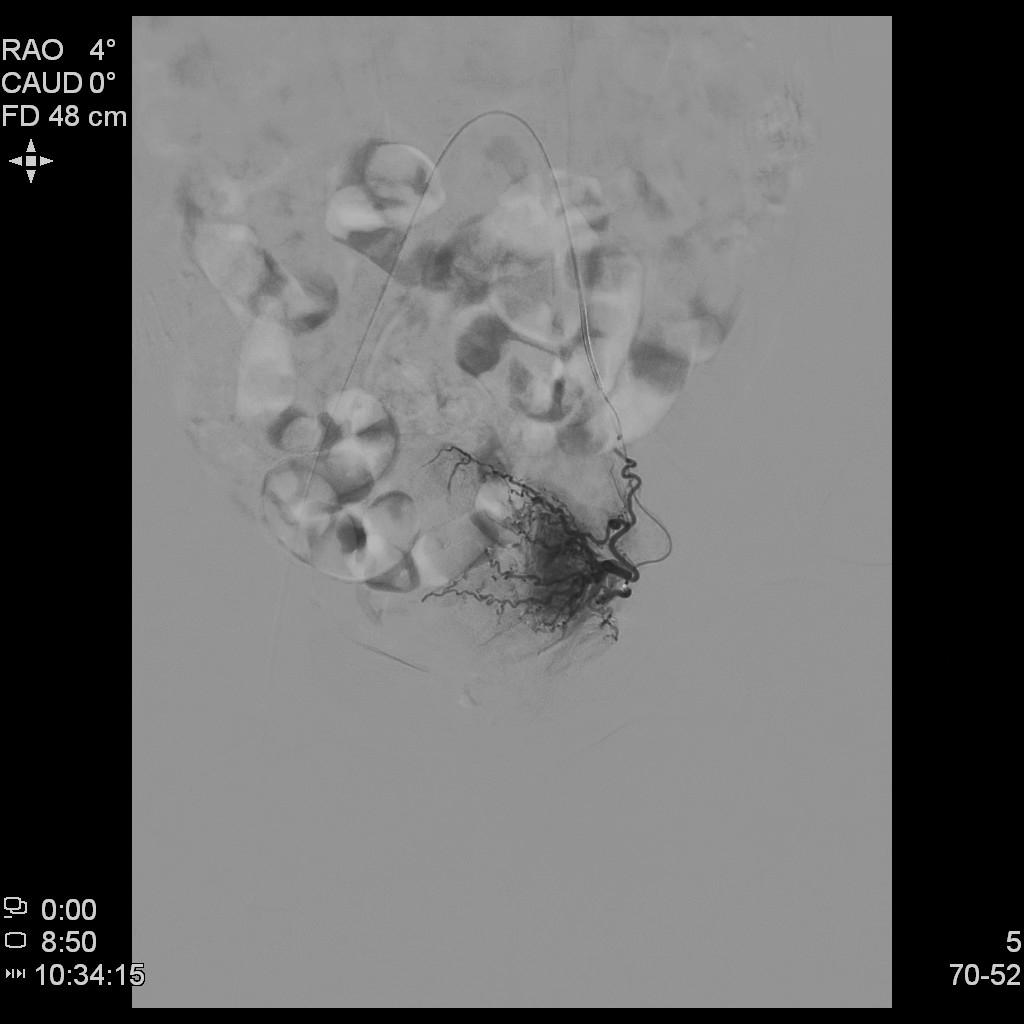

- 插管至右侧子宫动脉,显示子宫右侧病灶情况

- 插管至左侧子宫动脉,显示子宫左侧病灶情况

右侧子宫动脉造影

左侧子宫动脉造影

左侧子宫造影